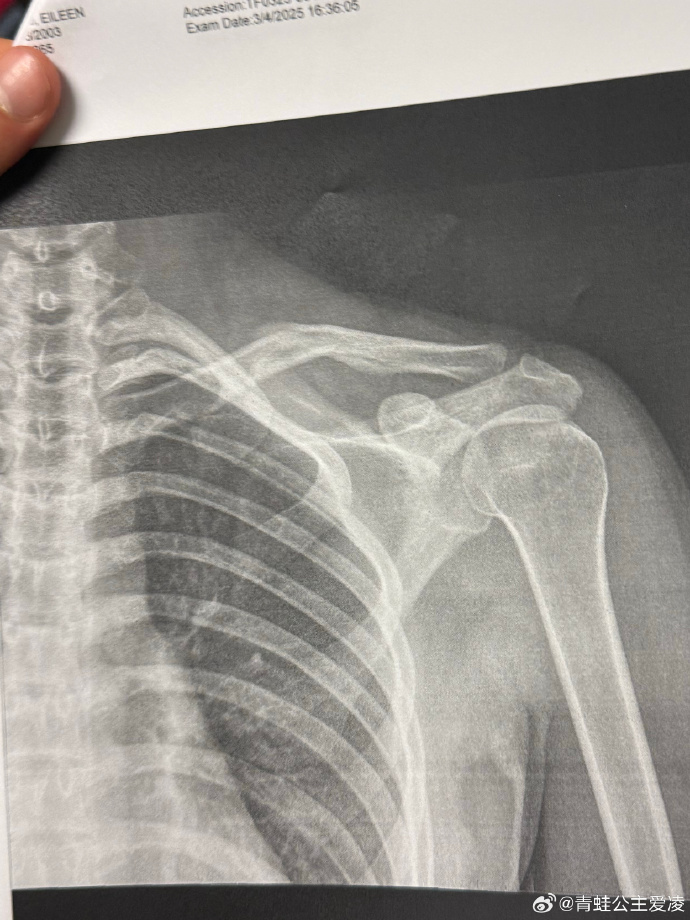

3月9日,中国自由式滑雪运动员谷爱凌在社交媒体晒出肩部骨折的X光照片,并配上一个心碎的表情,随后相关话题登上热搜。

X光照片显示的日期是3月4日,目前尚不得知谷爱凌本次的伤病是新伤还是旧伤。